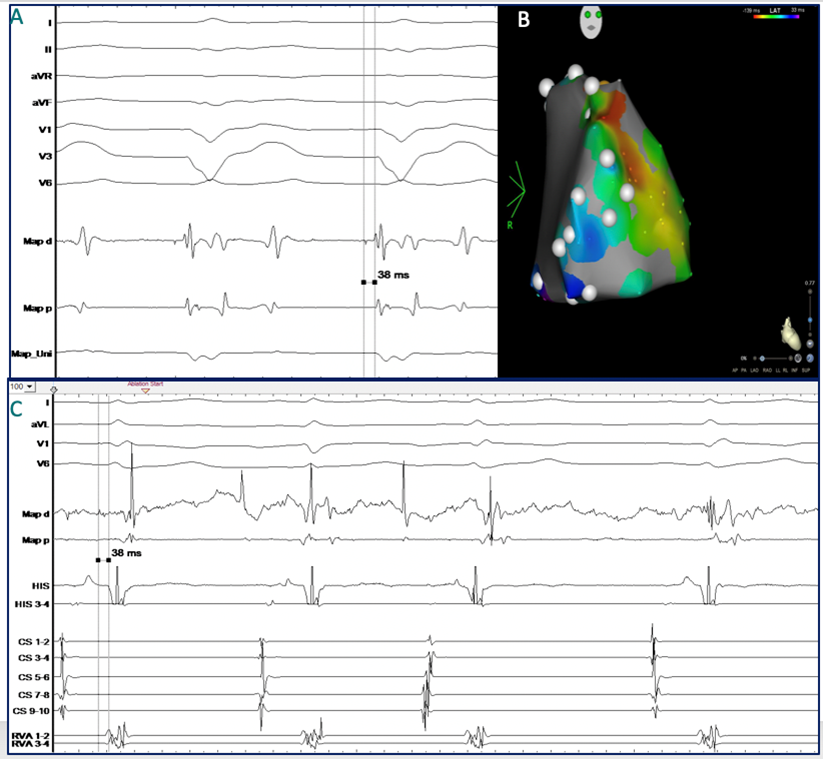

Abbildung 5: Ablation der Mahaim Faser

A)    Frühstes Signal mit Nachweis eines scharfen, „His“-ähnlichen Mahaim Potenzials im Bereich des superior-anterioren Trikuspidalklappenannulus

B)    Aktivierungsmap der frühsten ventrikulären Erregung entlang des Trikuspidalklappenannlus

C)    Erfolgreiche Ablation der Mahaim Faser mit Hochfrequenzstrom und Auftreten eines Rechtsschenkelblocks (Ableitung V1). Der CS-Katheter ist im             rechten Vorhof positioniert.